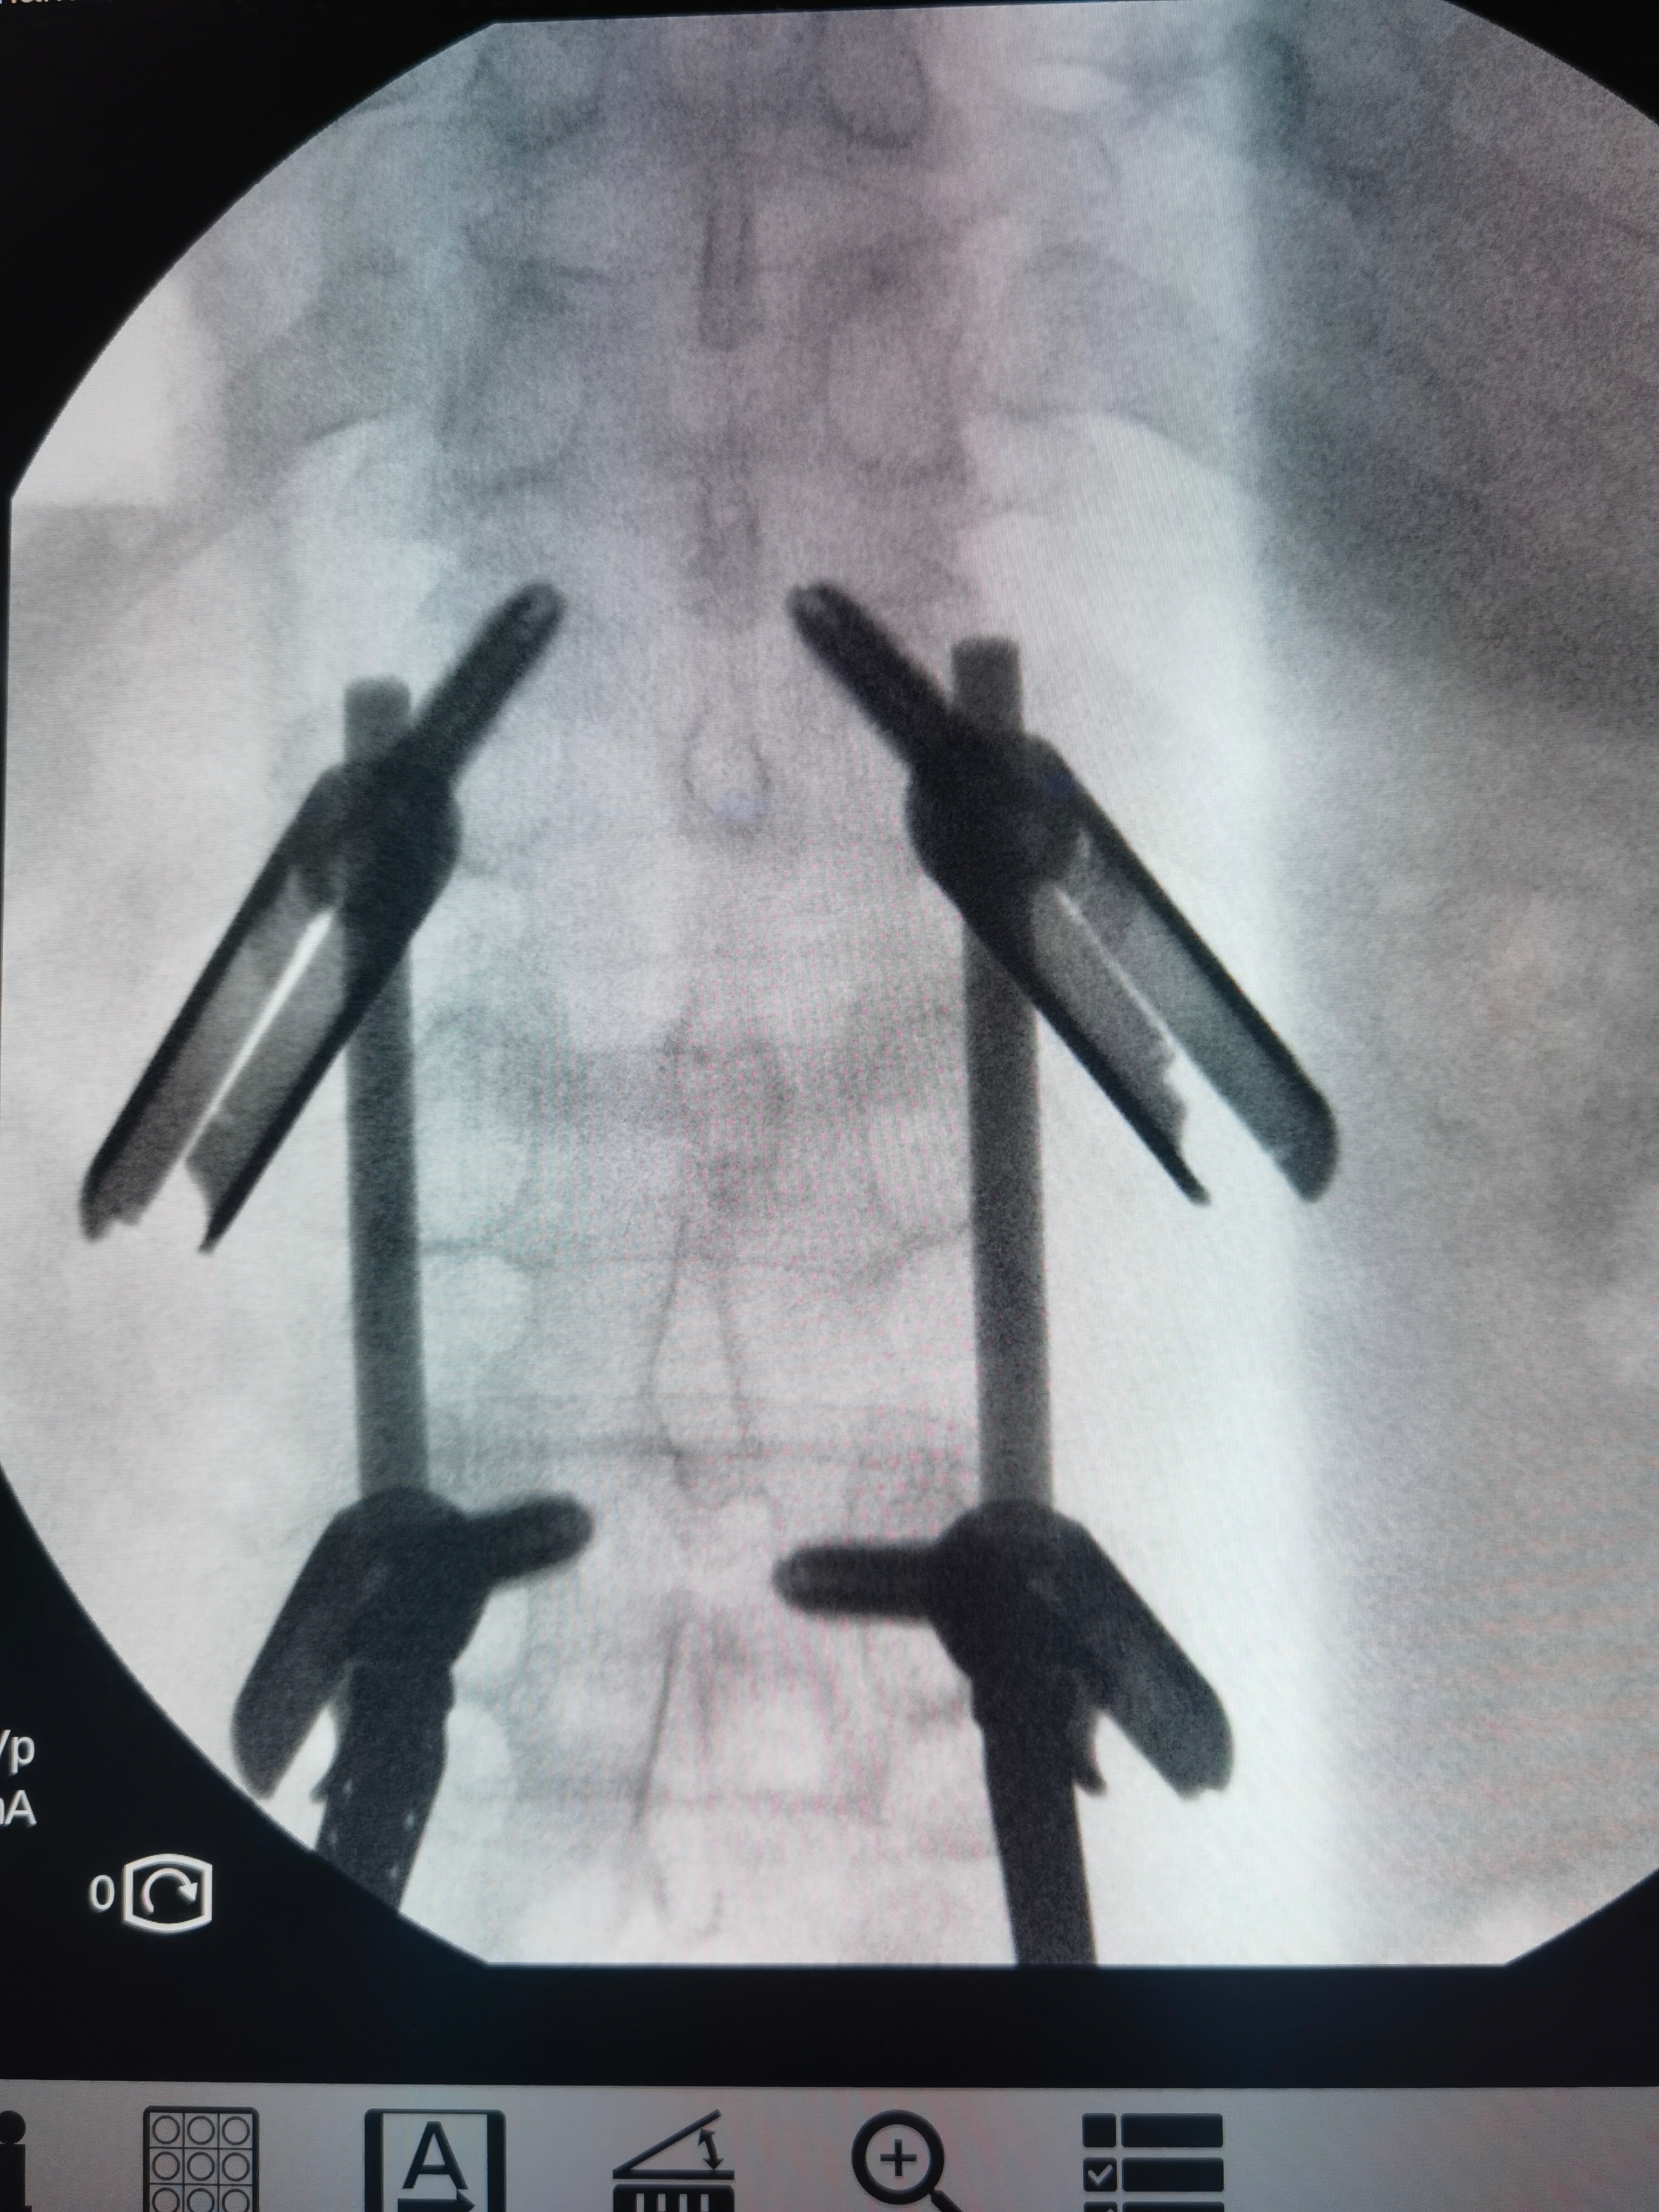

确诊为脆皮年轻人:小伙子今年41岁,参加公司团建去泰国玩儿。小船出海,风大浪大,几个颠簸,骨折,剧痛,只能躺着。同事三个人,两个骨折,另一个轻一点儿,去协和康复科保守治疗。我帮小伙子做了微创钉棒手术,4个小孔,完美复位固定。手术中发现骨头的确不行,类似60多岁女性。这种冻豆腐骨头,不建议保守治疗,越躺越疏松。脆皮天天见,天天坐班,下班躺床上刷手机,缺乏锻炼。。。大家一定要小心,可能是你,也可能是我。休假要去滑雪啥的,把保险买好。[笑cry]